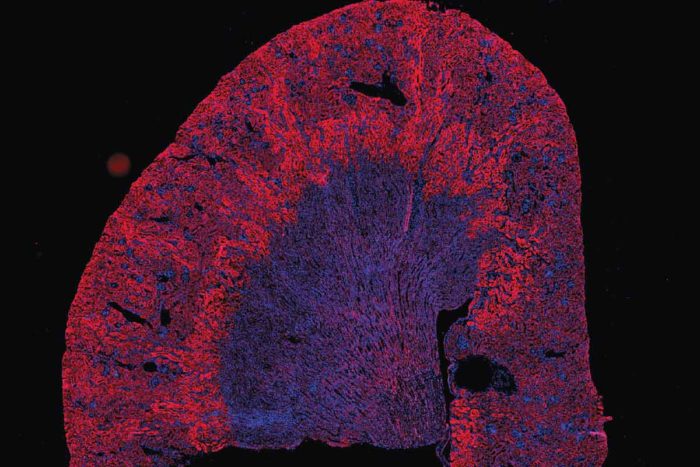

Making the invisible visible

Imaging center brings the science of life to light